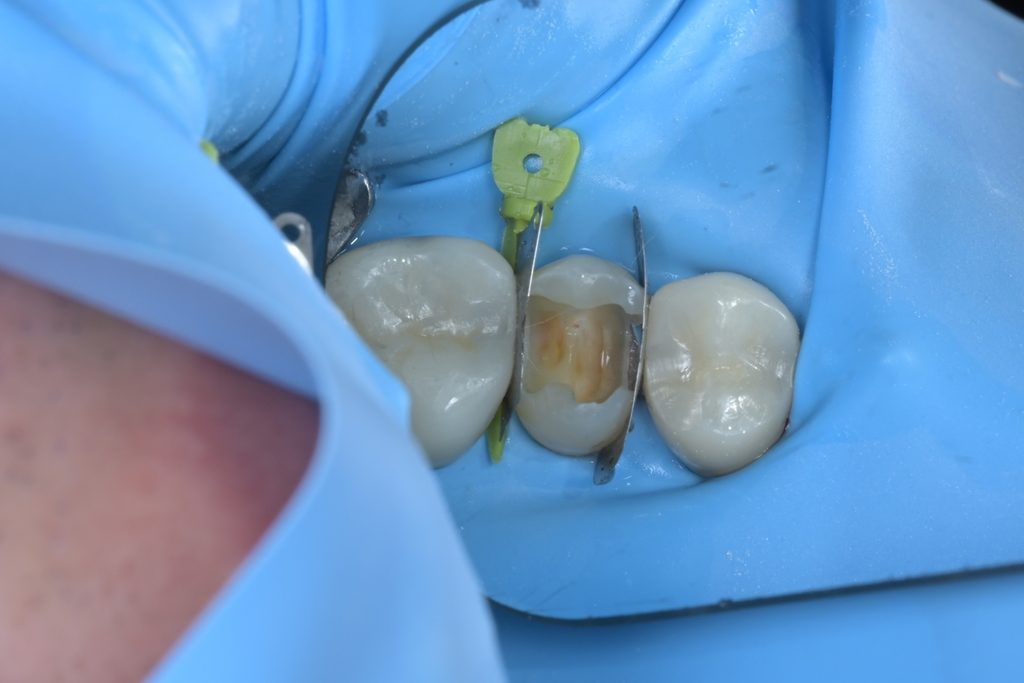

Step 4: MTA를 이용한 치수 보호

노출된 치수 부위를 생리식염수로 세척하고, 지혈을 확인한 후 MTA(Mineral Trioxide Aggregate)를 치수 노출 부위에 직접 접촉시켜 밀폐합니다. MTA는 수분이 있는 환경에서도 경화되며, 치수 조직과 생체적합성이 우수하여 상아질 브릿지 형성을 유도합니다.

Step 5: 레진빌드업 수복

MTA가 경화되면, 그 위로 복합레진을 이용한 레진빌드업을 시행합니다. 인접면부터 교합면까지 층층이 적층하며 원래 치아의 해부학적 형태를 정밀하게 재현합니다.